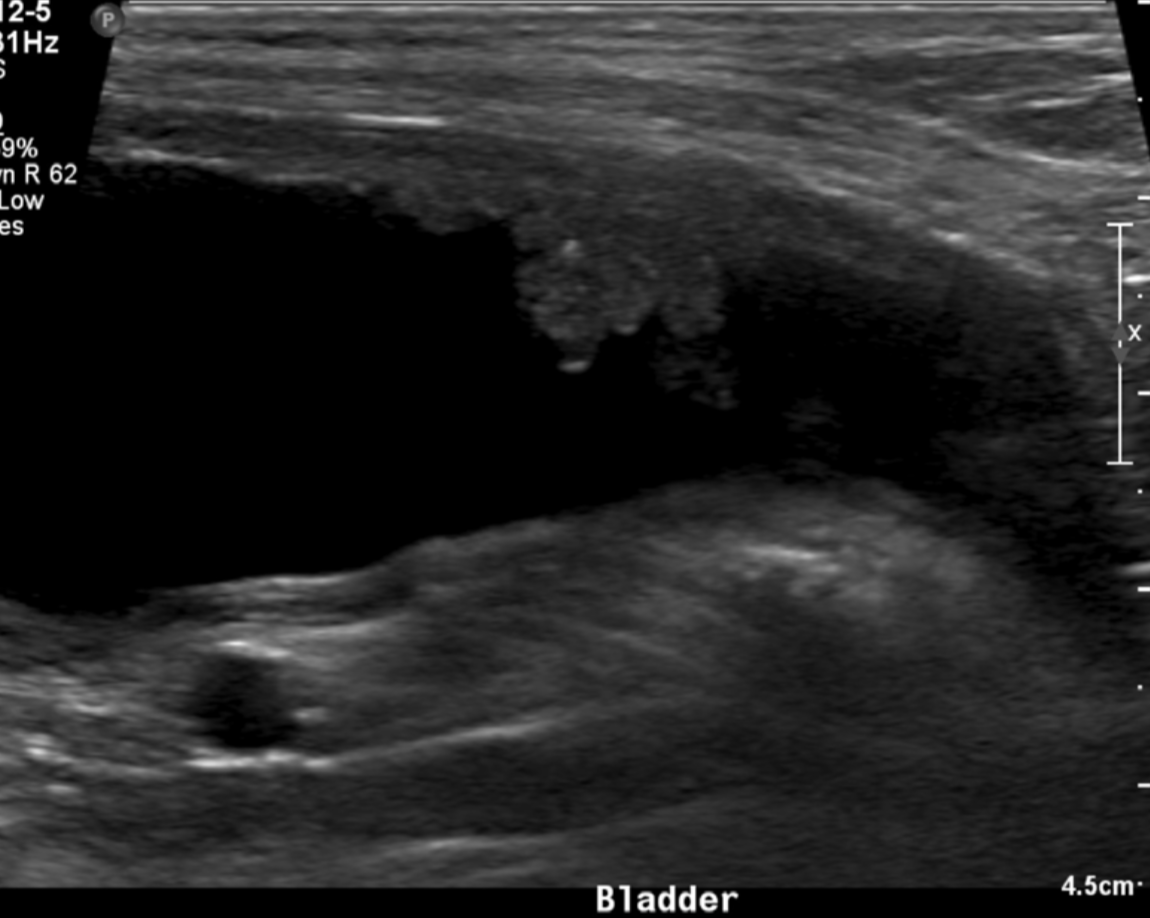

neoplasia of the bladder likes to affect what region

trigon and dorsal wall

OLD DOG bladder

TCC/neoplasia

key feature of bladder neoplasia on ultrasound

mass or polyp lesion in the trigon or dorsal wall